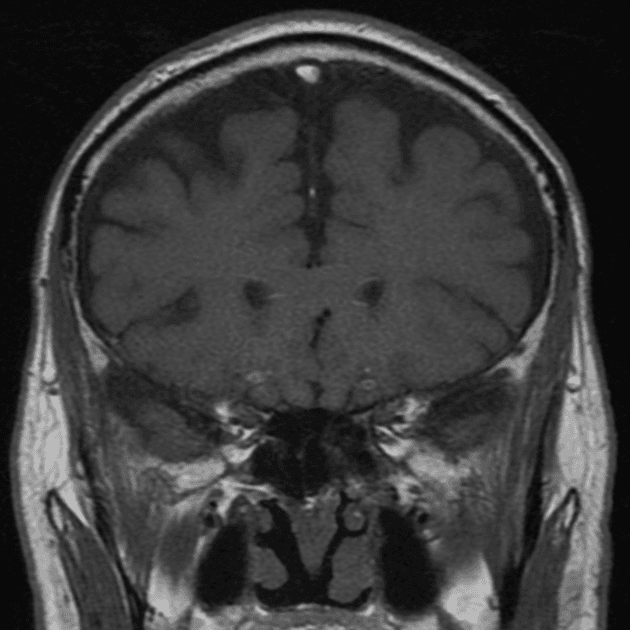

Chụp MRI sọ não phát hiện khối tổn thương dạng đặc, nhiều thùy (multilobulated, solid) nằm ở phần trước của não thất ba (third ventricle).

Khối tổn thương có tín hiệu đồng tín hiệu (isointense) trên hình ảnh T1W, tăng tín hiệu không đồng nhất (heterogenous hyperintense) trên hình ảnh T2W, không có hạn chế khuếch tán (no diffusion restriction), với một số vùng nhỏ có giá trị ADC thấp. Sau tiêm thuốc tương phản, khối cho thấy tăng quang mạnh (vivid enhancement) và đồng nhất (homogenous enhancement).

Hình ảnh MRI sọ não này thể hiện các đặc điểm hình ảnh điển hình của u nguyên bào dạng dây chằng (chordoid glioma).

U nguyên bào dạng dây chằng là những khối u độ ác tính thấp, phát triển chậm, hiếm gặp, xuất phát từ phần trước của não thất ba. Khối thường cho thấy kiểu tăng quang mạnh và đồng nhất. Vị trí đặc biệt và kiểu tăng quang gợi ý chẩn đoán trước mổ.